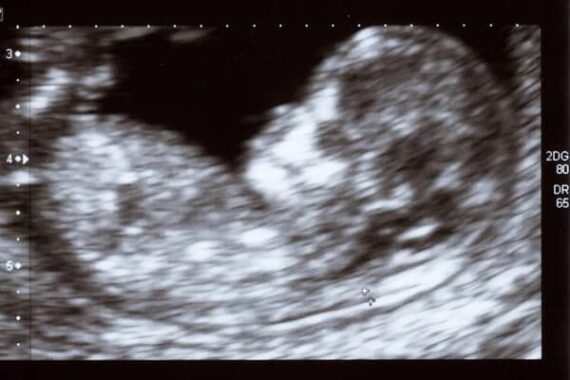

C’est un livre pour enfants et il vise les enfants de la maternelle et du primaire, mais son titre, et son contenu, sont aux antipodes de ce que devrait être la littérature enfantine : Abortion Is Everything, « l’avortement c’est tout ». Les petits ingurgitent à travers cette publication du Shout Your Abortion Movement (le mouvement : « Hurle ton avortement ») l’idée que l’avortement est un « superpouvoir ». C’est en tout cas ainsi que l’éditeur en fait la promotion sur les réseaux sociaux en attendant sa sortie prochaine : « Ce magnifique livre relié a été créé pour parler de l’avortement aux enfants. Abortion Is Everything s’adresse directement aux enfants de cinq à huit ans pour leur expliquer ce qu’est l’avortement, ce qu’il peut représenter et pourquoi certaines personnes y ont recours. Dans un langage accessible et inclusif, Abortion Is Everything présente l’avortement comme la concrétisation d’un super-pouvoir propre à l’être humain : notre capacité à imaginer l’avenir et à faire des choix qui nous mènent vers la vie que nous envisageons. L’avortement est un outil qui permet aux êtres humains de façonner leur destin et qui a façonné le monde entier qui nous entoure. » Si on voulait créer le syndrome du survivant et la peur du monde qui les entoure chez ces petits, on ne s’y prendrait pas autrement. A vomir.